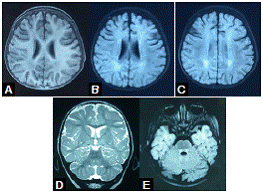

La resonancia magnética (RM) cerebral simple practicada a los 10 meses, mostraba leucoencefalopatía parieto-occipital, e hiperintensidad del tracto tegmental central y de los núcleos delgado y cuneiforme (figura 1). En el electroencefalograma (EEG) se evidenció actividad epileptiforme focal témporo-parietal izquierda. Con los estudios metabólicos se descartó aminoacidopatía, aciduria orgánica, leucodistrofia metacromática y enfermedad del peroxisoma.

A partir de los 18 meses de vida, la niña no volvió a tener convulsiones, pero en la RM cerebral persistía la hiperintensidad del tracto tegmental central, aunque habían desaparecido las lesiones de la sustancia blanca parieto-occipital (figura 2). A los dos años de vida, recibía un solo medicamento anticonvulsivo y presentaba rasgos autistas, en tanto que en el electroencefalograma y la RM cerebral ya no aparecían las anomalías previamente descritas (no se muestran las imágenes).